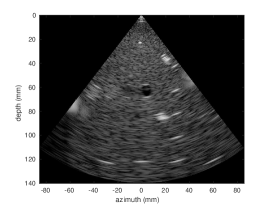

3.2 Results

Quantitative results for the cardiac test set are summarized in Table 1. We show a major improvement in decorrelation and SSIM for both and MLA. The corrected MLA performance approaches that of MLA, suggesting the feasiblity of larger MLA factors. Figure 4 shows representative images from each imaging modality. We show that the correlation coefficients profile of the corrected and MLA approaches that of SLA.

![]() |

|

| (a) SLA | (b) MLA | (c) Corrected MLA | |

||

|||

| (d) MLA | (e) Corrected MLA |